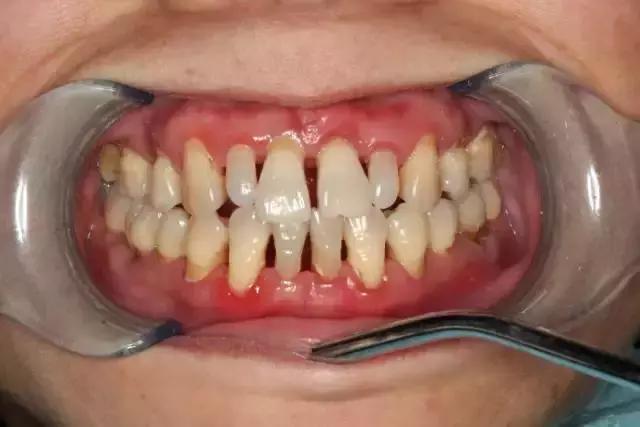

大多数情况都是来自外在的因素(如细菌)导致的出血,比如刷牙不到位导致牙菌斑、牙结石等附着在牙齿表面,长期刺激牙齿周围的牙龈及牙周组织。

虽然起初没有任何的不适症状,但是会使牙龈由健康慢慢变为炎症状态:充血红肿、由坚韧的质地慢慢变得很脆,一旦受到刷牙和咀嚼时的机械摩擦就极易出血。

还有一些是因为不太理想的假牙或者补的牙有一些不光滑的地方导致经常有食物嵌塞,这些都极易导致细菌聚集而刺激牙龈,发生炎症性出血。